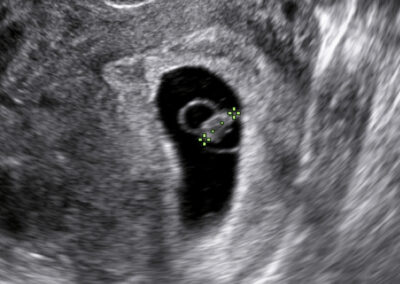

Vyšetření časného těhotenství NT screening Downova syndromu v 1.trimestru Screening vrozených vad ve 2. trimestru Screening ve 3. trimestru